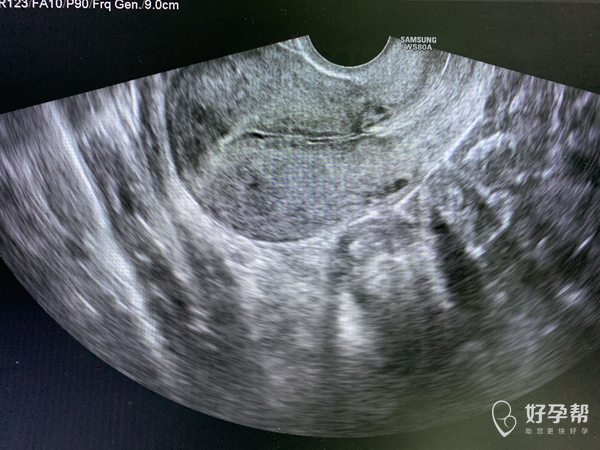

医生帮我看下我重新进入周期了年初四姨妈来了没几天很少量没有了,然后年后去看医生问医生然后做了阴超21号内膜6没有宫腔分离,医生让我礼拜一吃地屈孕酮片吃十天但是吃了第五天就开始来了但是量不多一开始因为吃药原因姨妈颜色咖啡色的,但是后面第五天一坨血浆一样下来,前几天量很少,我现在重新进入周期了,我以前从来没有的,就打针后面两次阴超有宫腔分离,

宫腔分离的主要原因可能有宫腔积液。一般是因为炎症引起的,医生让你吃地屈是希望你的内膜好好剥脱一下,利于重新进入周期,你说的一坨血浆一样的,如果有烂肉一样的组织,那就是剥脱的内膜。按医嘱来吧